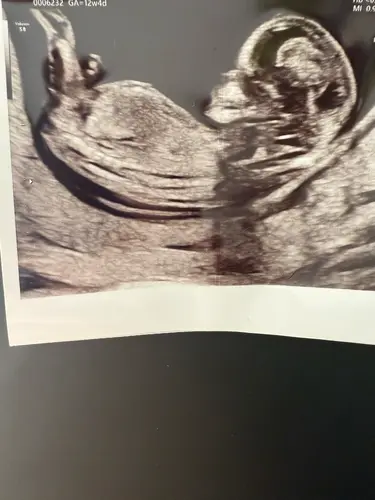

Ik heb 2 echo’s waarop je (volgens mij) de nub kan zien alleen nu zie ik op de ene een meisje en op de andere een jongen…… wat denken jullie? Dit is de eerste echo

Dit is de tweede